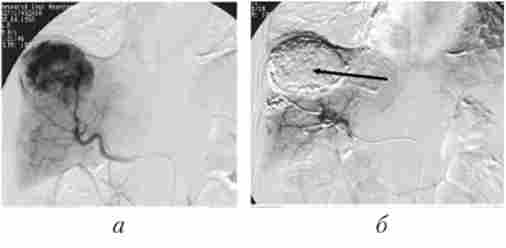

Після артеріогепатікографіі і оцінки кровотоку в судини, що живлять пухлину, вводиться емболізат - суспензія масляного контрастного (ліпіодол) і протипухлинного препаратів (доксорубіцин 40-60 мг, мітоміцін 10-15 мг) (рис. 16.10).

Ангіограми печінки хворий ГЦК

Мал. 16.10. Ангіограми печінки хворий ГЦК:

а - селективна ангіограма печінкової артерії, визначається гіперваскулярний вузол у правій частці печінки; б - оглядова рентгенограма, компактне накопичення масляного контрастного препарату в пухлинному вузлі (показаний стрілкою)